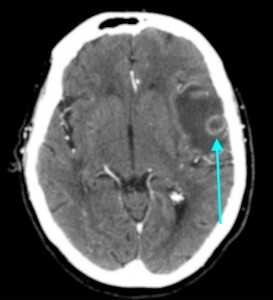

Метастазы головного мозга, фото. На КТ с контрастным усилением у пожилой пациентки (в верхнем ряду слева) с жалобами на головные боли выявлены множественные объемные образования в левом полушарии мозга, интенсивно накапливающие контрастное вещество. Образования имеют характерную форму в виде «кольца». На изображениях в нижнем ряду и вверху справа определяются множественные очаги в головном мозге: отчетливо видны округлые образования с более плотным «ободком» по периферии, располагающиеся в левой теменной доле.